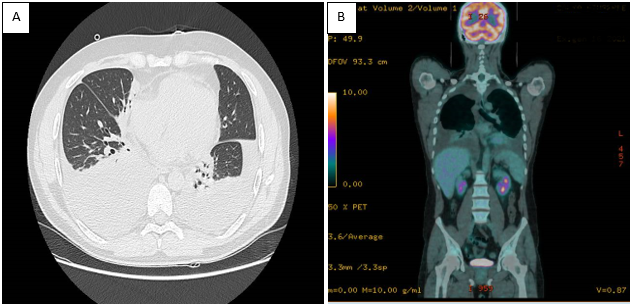

Isolated pauci-immune pulmonary capillaritis associated with an extensive bilateral hemothorax and pleuro-pericarditis